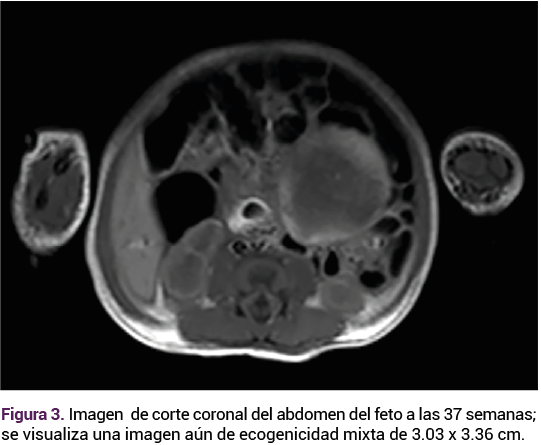

El ultrasonido obstétrico reportó: feto único, vivo, con frecuencia cardiaca de 135 lpm, peso estimado de 2767 g en el percentil 71, placenta fúndica grado II de Granum y líquido amniótico cualitativamente normal. Los genitales se advirtieron fenotípicamente masculinos, sin evidenciar el testículo derecho en la bolsa escrotal. La imagen ecogénica era mixta respecto de la ecogenicidad de los tejidos circundantes de 29 x 23 mm de una tumoración móvil adyacente al colon, cercana a la pared abdominal. La aplicación de Doppler color fue negativa, sin efecto de masa hacia otras estructuras abdominales, sin líquido libre o gas. El resto de la exploración transcurrió sin alteraciones. Figuras 1 y 2.

<strong>Figura 1</strong>

Figura 1.

Ante las características ecográficas de la tumoración se decidió la conducta expectante, con seguimiento ecográfico. A las 37 semanas el feto continuaba con una frecuencia cardiaca de 140 lpm, peso de 3186 g, percentil 84, placenta fúndica, líquido amniótico cualitativamente normal. Sin embargo, con un aumento notable del tamaño de la tumoración intraabdominal, ahora 1 cm más grande, respecto del rastreo previo.